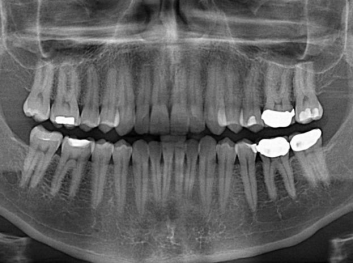

損壞的牙齒如何自我修復(fù)?近日,來(lái)自哈佛大學(xué)和諾丁漢大學(xué)的研究人員研發(fā)了能夠刺激牙齒干細(xì)胞再生的新型生物材料,而這種新材料研發(fā)成功的背后,正源于他們對(duì)牙齒如何實(shí)現(xiàn)自我修復(fù)這個(gè)課題的不斷探索。

據(jù)美國(guó)期刊《大眾科學(xué)(Popular Science)》報(bào)道,此種新型生物材料,不僅可以有效地取代傳統(tǒng)補(bǔ)牙填充物,刺激牙齒干細(xì)胞再生,患者也有望無(wú)需再接受根管治療,使蛀牙患者免除牙根感染或牙髓壞死的苦惱,一個(gè)全新的牙齒治療時(shí)代即將來(lái)臨。

Adam Celiz,是來(lái)自諾丁漢大學(xué)的研究人員,他和同事開發(fā)的這種新型合成生物材料,能刺激干細(xì)胞在牙髓部的生長(zhǎng)。與普通材料一樣,這種合成材料被填充到牙齒并用UV光硬化。

在體外測(cè)試中,材料刺激干細(xì)胞進(jìn)入牙本質(zhì)的增殖和分化速度,促進(jìn)形成牙齒骨組織。研究人員認(rèn)為,一旦材料在受損牙齒中應(yīng)用,這些干細(xì)胞可以自動(dòng)修復(fù)來(lái)自填充物上的損壞。在本質(zhì)上,該生物材料將使牙齒自愈。

在未來(lái),Adam Celiz說(shuō),可再生材料能制成各種填充物以便受損牙齒的自身治愈,降低補(bǔ)牙失敗率,甚至?xí)蟛糠秩藢?duì)根管治療的需要。